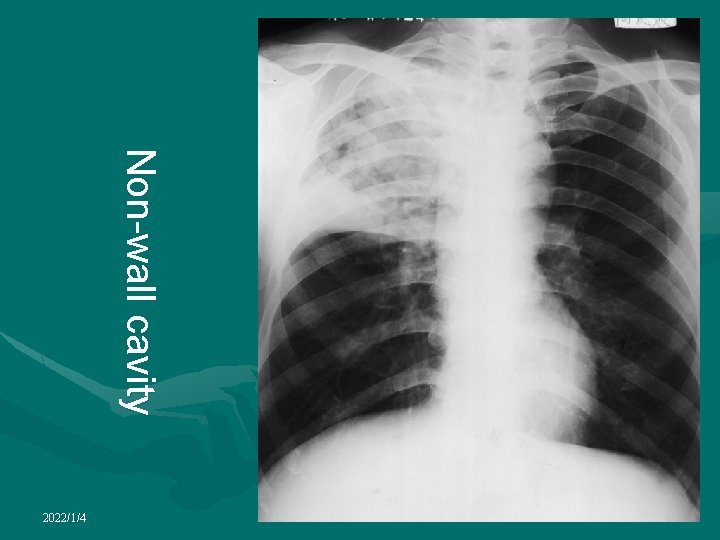

Cavity ¦non- wall cavity: ¦Thin-wall cavity: thickness of cavity wall is less than 3 mm, Tuberculosis ¦Thick-wall cavity: thickness of cavity wall is more than 3 mm, Tuberculosis, abscess, cancerous 2022/1/4

Cavitation • Occurs in both benign and malignant nodules • Benign cavitary nodules generally have smooth, thin walls, whereas malignant nodules typically have thick, irregular walls • Most nodules with a wall thickness greater than 16 mm are malignant, whereas those with a wall thickness less than 4 mm are usually benign 2022/1/4

Non-wall cavity 2022/1/4